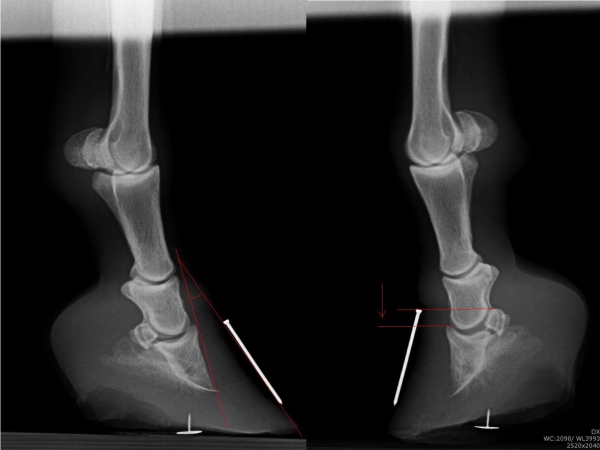

Chronicky schvácené kopyto

Podotrochleóza

Sam - kladrubský hřebec s laminitídou a výhřezem kopytní škáry, teď krásně chodící a to hlavně díky velké pomoci podkováře, p.Schmidta